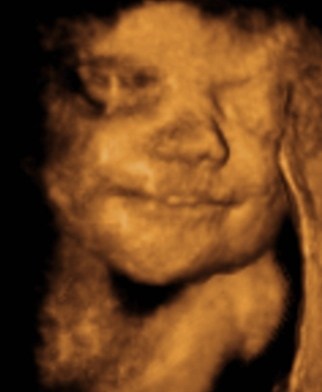

Ufødte børn smiler i maven

"Nogle mener, at nyfødte, der griner i virkeligheden skærer ansigt eller har ondt i maven. Men nu mener forskere, at børnene begynder at smile, før de overhovedet er blevet født. Fosteret udvikler en række ansigtudtryk i livmoderen i sådan en udstrækning, at det er muligt at identificere udtryk for latter og gråd, lyder det i et nyt studie foretaget af forskere fra flere engelske universiteter. Resultaterne er publiceret i tidsskriftet PloS ONE. Det er angiveligt første gang, at det er lykkes en gruppe forskere at vise, at helt tydelige ansigtsudtryk udvikles i moderens mave."

Vedhæftede fotos (klik for at se i fuld størrelse)